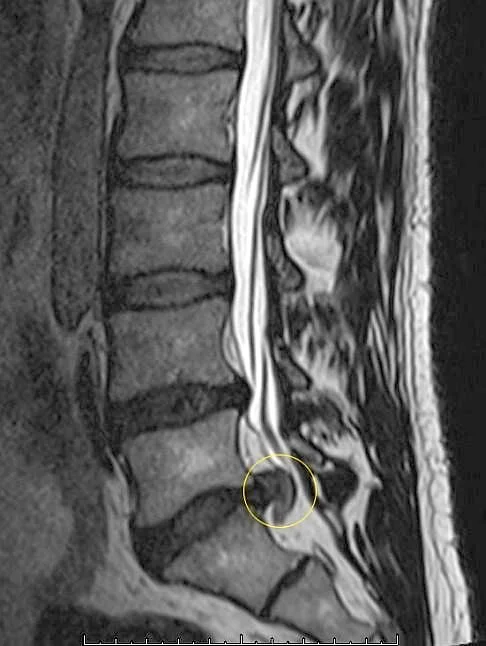

Die häufigsten Bandscheibenvorfälle sind in der unteren Hals- und unteren Lendenwirbelsäule zu finden. Bezeichnet werden sie nach der Höhe der Bandscheibe, wobei hier immer ein Buchstabe für die Betroffene Region vorgestellt wird:

MRT: Bandscheibenvorfall L5/S1

Bspl. Bei einem Diskusprolaps C5/C6 ist nun also die Bandscheibe zwischen 5. und 6. Halswirbel betroffen, während ein Vorfall L5/S1 den Diskus zwischen 5. Lendenwirbel und Kreuzbein meint.